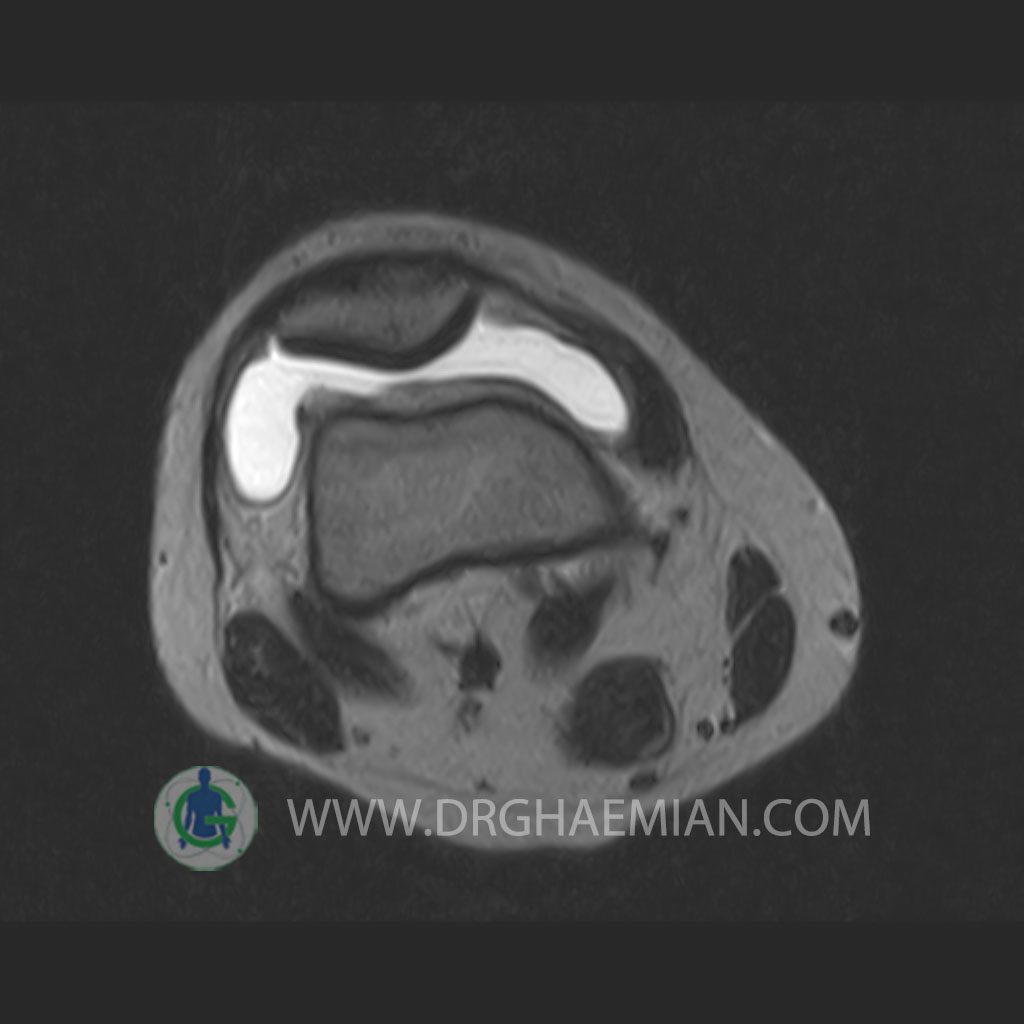

RIGHT KNEE MRI

(Without contrast)

Technique: Sagittal T1, T2 , Axial GE , coronal & sagital fatsat .

– Knee joint effusion with soft tissue swelling around the knee

– Grade 2 signal change in P.H. of medial meniscus with partial tearing of posterior root & meniscal extrusion

– Grade 2 signal change in P.H. of lateral meniscus with meniscal extrusion

– Complete tearing of ACL ( femoral detachment ) with bone bruise in plateau of tibia

are seen